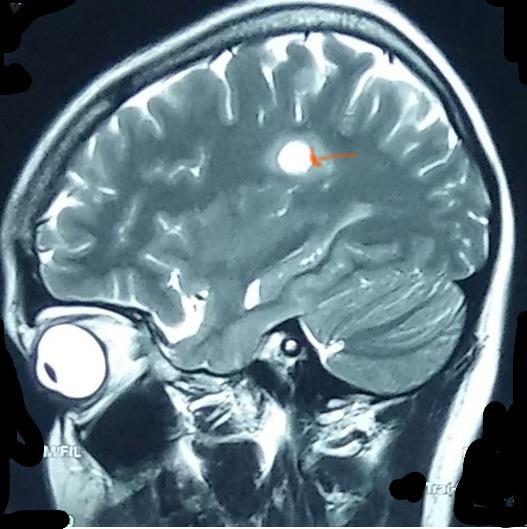

One year ago, she had right side eye pain for a week duration and no abnormalities were detected upon ophthalmology assessment and was prescribed steroid eye drops with no improvement. However, her pain responded to non-steroidal anti-inflammatory drugs (NSIAD) in 5 days. One week later, she developed double vision. Therefore, she was subjected to an MRI of brain and spinal cord. The results showed periventricular and corpus callosum demyelinating lesions characteristic for multiple sclerosis (figure-1 & 2) and also found to have multiple demyelinating lesions in multiple levels of the spinal cord at C2, C5, T1, T5, T7, T9 and T12 levels (figure-3).

Figure-1: Demyelination lesions in the periventricular areas

Figure-2: Demyelination lesion in the corpus callosum